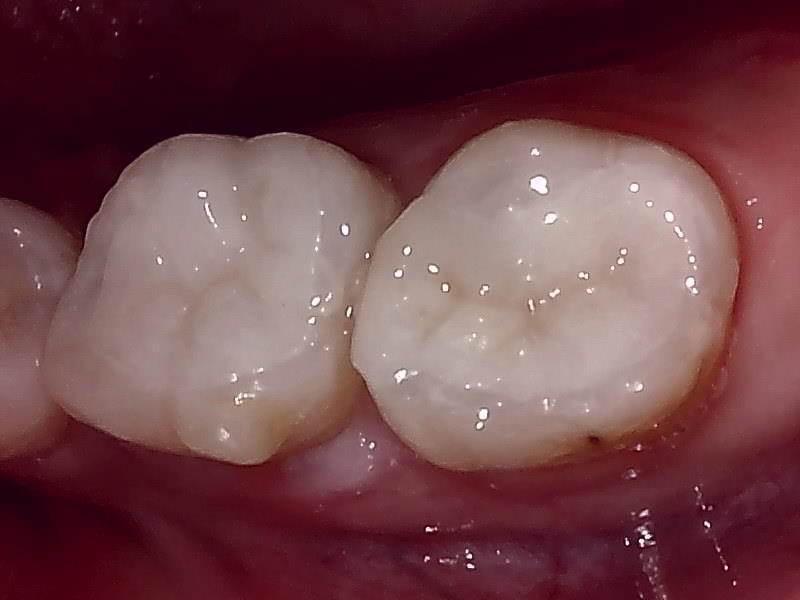

写真; セラミックインレー装着後の歯冠の仕上がり(咬合面観)